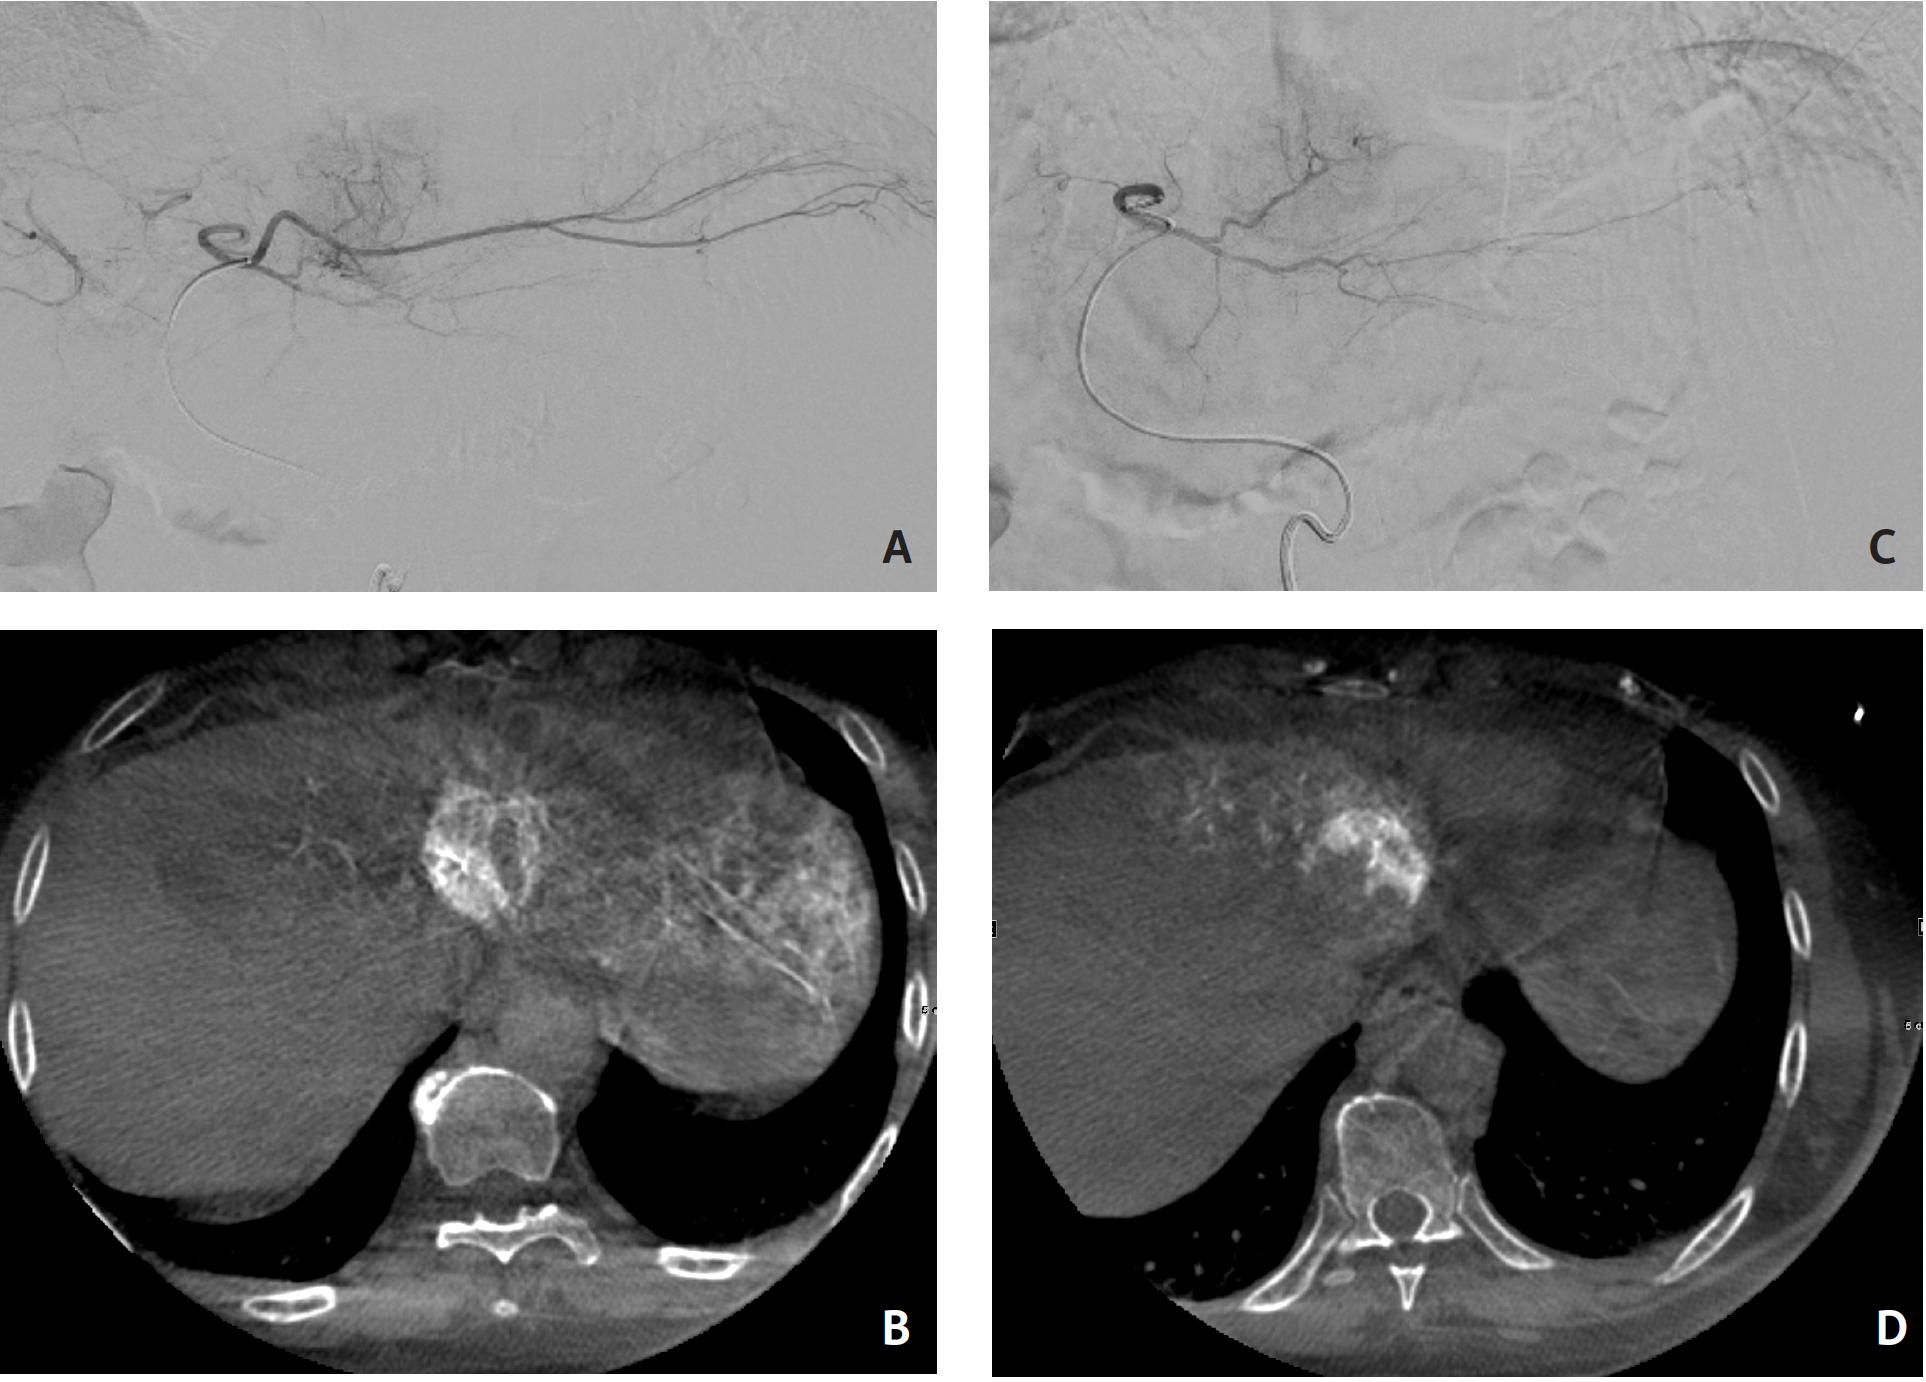

As an example, I recently had a patient who was undergoing treatment for hepatocellular carcinoma. I used the cone-beam CT feature to scan the liver with the Angio machine and I found that the artery I thought was supplying the tumor supplied only part of the tumor, while another artery supplied the other half of the tumor. Without this specialized software, I would have done the procedure on only the first artery, brought the patient to follow-up, and discovered that only half the tumor was treated, necessitating another treatment session. Because I had the cone-beam CT, EmboGuide software, and Fusion software (Philips), I was able to fuse multiple cone-beam CT images together to show that the entire tumor would be covered by injecting into 2 arteries. Philips software enabled me to optimize this patient’s treatment in only 1 session. Each tumor is different, and the software allows us to provide a personalized approach to each patient.